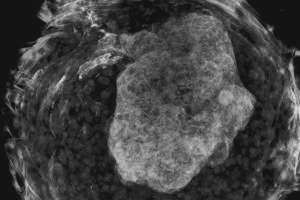

科学家利用细胞的自我组织性构建心脏。图片来源:《新科学家》 如果通过显微镜观看,你会看到一段人类心脏跳动的影像资料,每个心脏都在驱动着其心室运动。这些微型器官的直径仅有1毫米,它是科学家首次利用单独干细胞制成的三维“心脏形”器官。 “利用肉眼看不到这些心脏的收缩,所以我们把它们叫作微观心脏。”美国加州大学伯克利分校的Zhen Ma说。这些器官以前也曾被制作过,但都是利用现存的结构把新细胞固定就位,比如由一个供体心脏被剥离细胞之后留下的胶原蛋白基质制成,抑或是利用3D打印制作而成。 Ma通过让普通皮肤细胞回转至原始的、类似胚胎细胞的方式,利用诱导多能干细胞形成心脏器官。通常情况下,研究人员会单独利用生长因子促使这种干细胞形成其中器官的专门细胞,但是Ma的研究团队利用了另外一种技术。 为了模拟出通常告诉胎儿干细胞可以在哪里生长以及不能在哪里生长的物理作用力,研究人员通过在培养皿中打孔,蚀刻了一种化学上的“禁止通行区”。这些孔可以让干细胞积累成恰当的外形。 这一过程通过模仿当真正的心脏在发育胚胎中发生的情况,对细胞的形状进行了改变。因此,那些位于孔中心的细胞变成了一种被称为心肌细胞的跳动心脏细胞。心肌细胞则被类似皮肤细胞的纤维母细胞包围在内,纤维母细胞形成了心脏的结缔组织。更显著的是,心肌细胞会生长并形成圆顶形的腔体——即微观心室。 “我们的模型在利用细胞的自我组织性构建心脏方面迈出了第一步,而且不需要任何外部的三维支撑材料。”Ma说,该研究的最终目的是构造出真实大小的心脏器官。 科学家利用干细胞制作出微观心脏